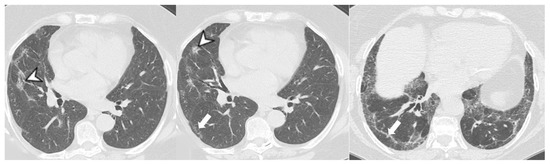

4.2.1. HRCT Findings of Patients with Anti-ARS Abs

| Lesions | GGO, reticulations, consolidations | consolidations, GGOs | |

| Distribution | Homogeneous; lower lung lobes, along bronchovascular bundles and lung periphery; loss of volume of lower lobes | Patchy; peripheral lower lobes or along the bronchovascular bundles | |

| CT pattern | NSIP OP NSIP-OP UIP DAD-unclassifiable | 50% 20% 25% 10% +/− | 20% 50% 25% <5% ++ |